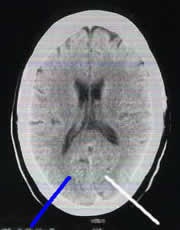

alle CT-Bilder